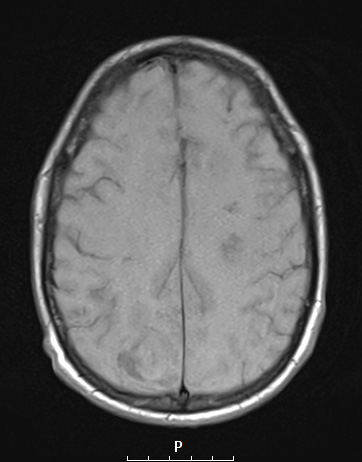

12A2 Abscess (Case 12) T1NoC A - Copy

Lesions are mildly hypointense in this T1-weighted scan without contrast.